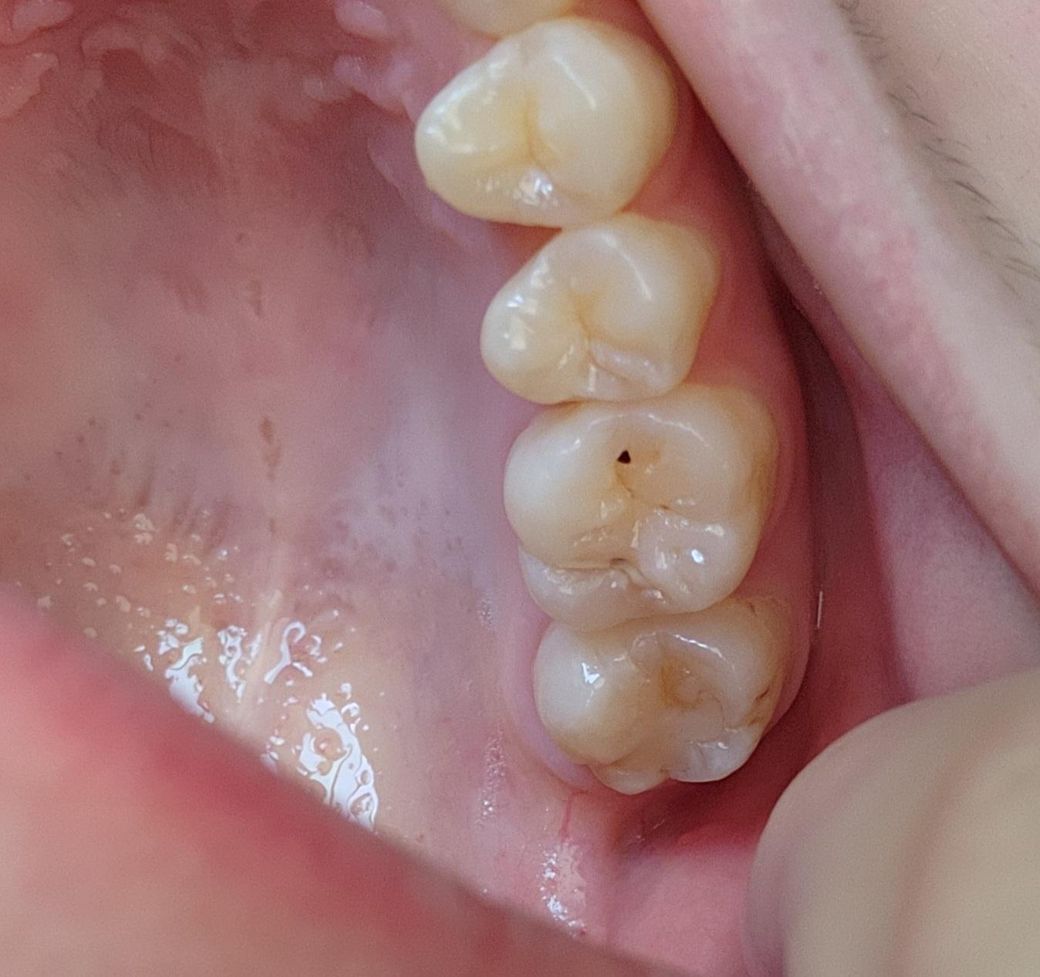

충치가 어느 정도로 심한 걸까요..ㅠㅠㅠ

충치인 것 같은데 각각 어느 정도로 심한 건지를 모르겠어서 질문드립니다ㅠㅠ 다음달에 치과를 방문할 예정이기는 하나 어느 정도로 보이는지 궁금해서요..ㅠㅜㅠㅠ

충치가 심한거 같진 않습니다. 간단한 충치치료를 하시면될것같으니 치과에 가셔서 검진을 받아보세요.

사진으로 볼 때는 충치가 깊어 보이지 않습니다. 작은 형태로 인해 충치의 경우에는 간단하게 치료를 할 수도 있습니다. 자세한 확인을 위해서 치과에서 진료를 받아보는 것을 권유드립니다

위 사진으로는 판별하기는 애매하지만 심한 정도로 보이진 않습니다. 치과내원해보시면 됩니다.

기존에 떼웠던 것이 떨어진 것이 아닐까 싶습니다 사진상으로 보기엔 깊은 충치는 아닌것 같으나 어쨌든 홈이 파여있어서 해당부위 음식물이 끼지 않도록 처치는 필요할 것 같습니다

충치가 현재 어느정도 꽤진행이 된 상태로 보입니다. 정확한 깊이나 정도는 진료를 통해 확인이 가능하기에 치과 진료를 빠른시일내에 받길 권합니다.